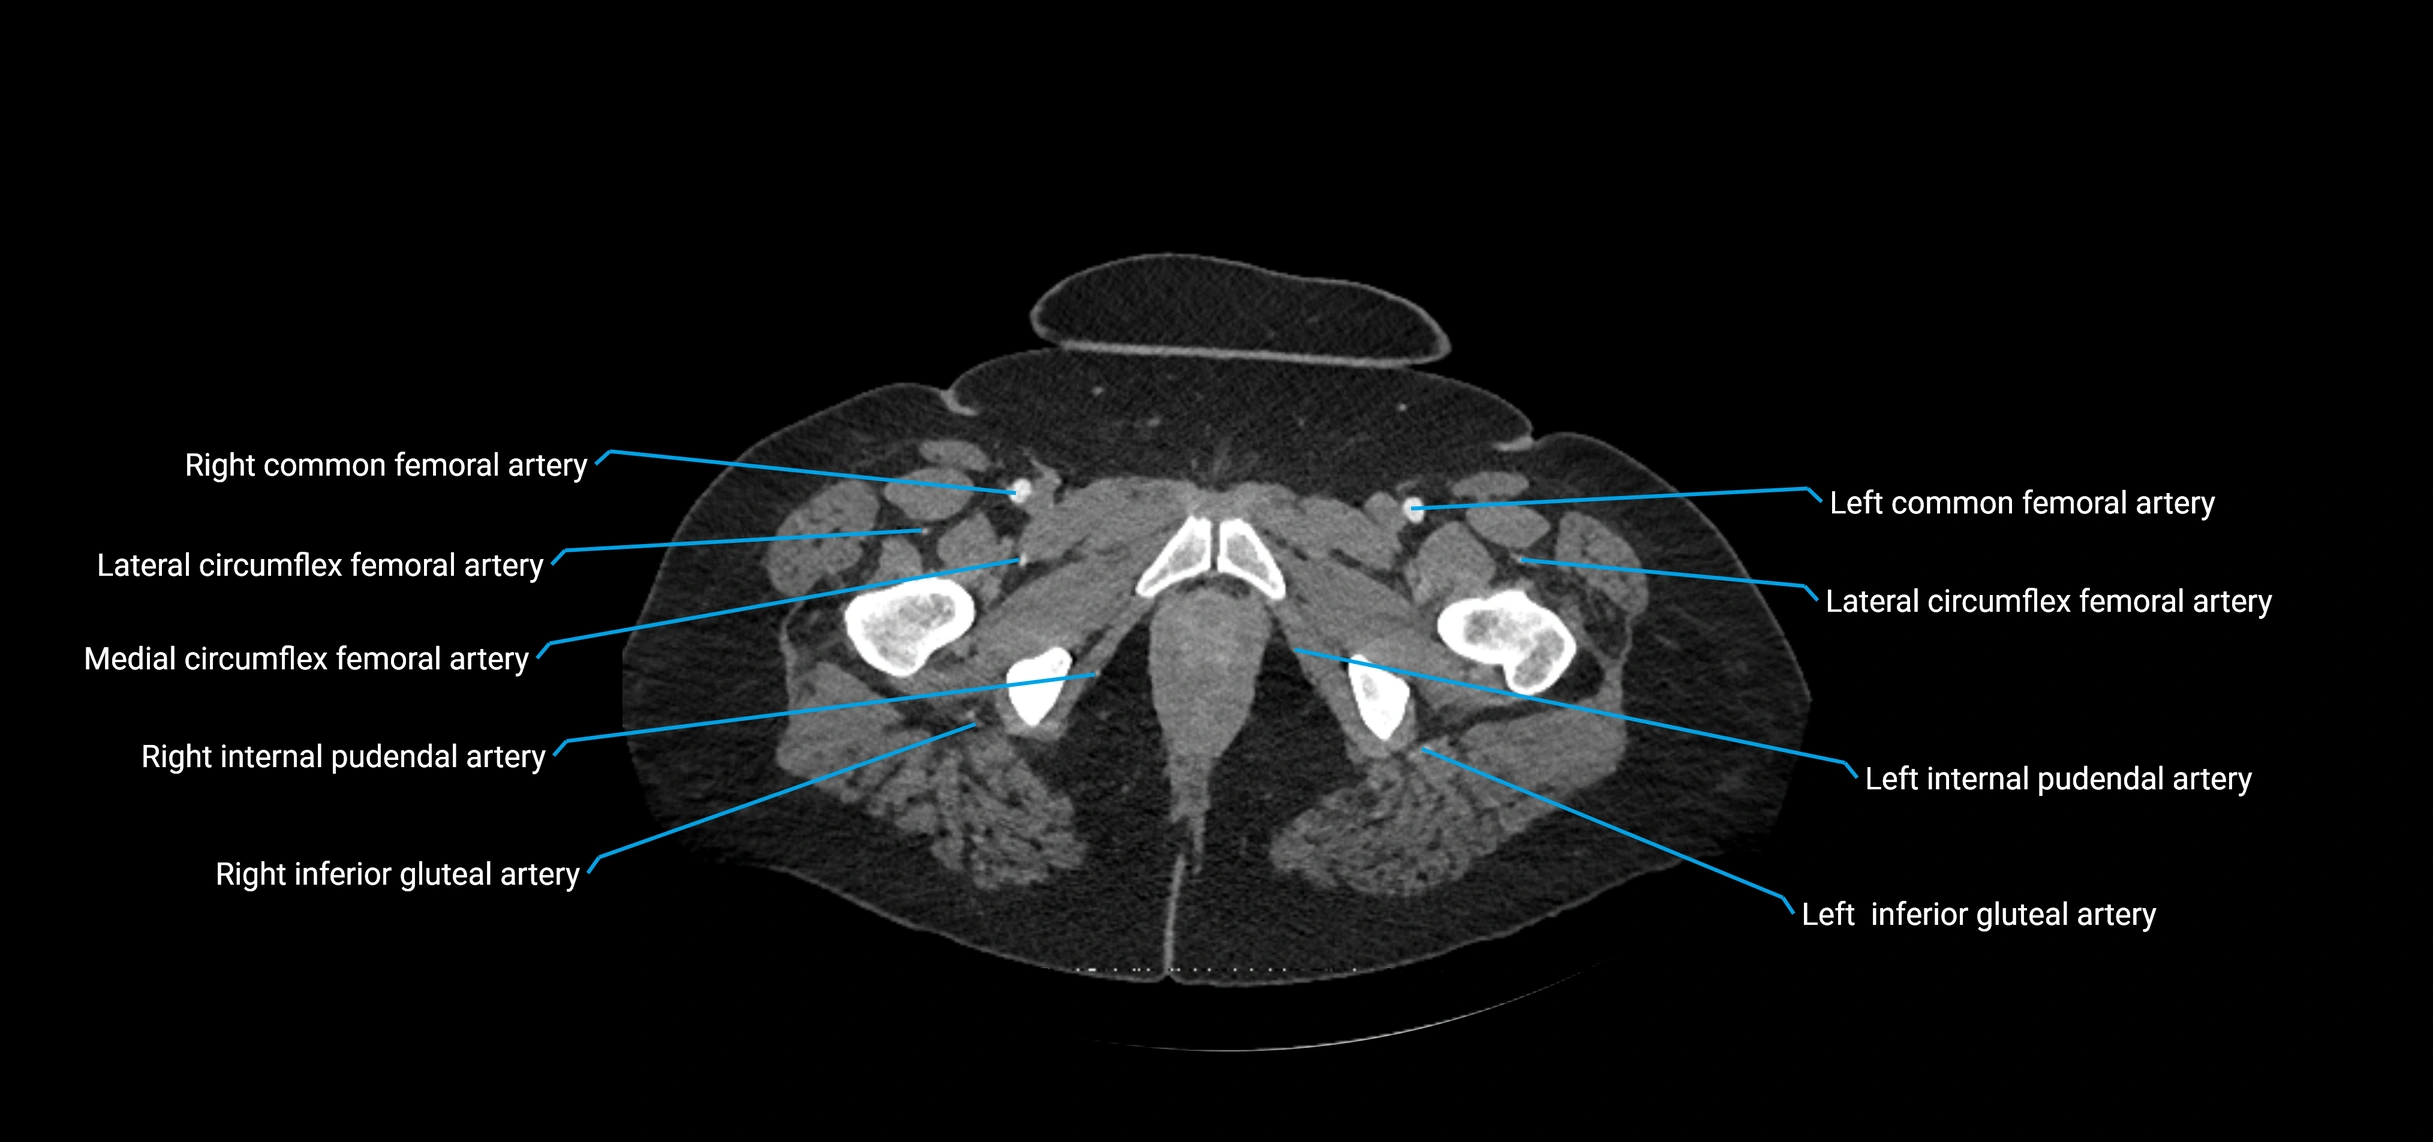

Contrast-enhanced CT (CTA):

• Gold standard for abdominal aortic imaging

• Provides excellent detail of lumen, wall, aneurysm, thrombus, and branch vessels

• Multiplanar and 3D reconstructions help in aneurysm measurement, stent graft planning, and dissection evaluation

• Detects acute rupture, traumatic injury, or occlusion with high sensitivity